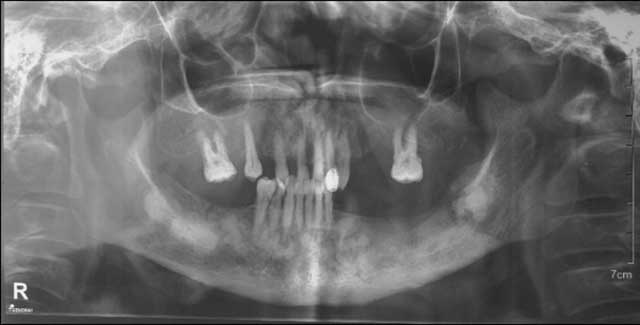

Fig.3 : Radiographie Panoramique.

La radiographie panoramique montrait une image mixte radio-opaque entourée d’un halo radioclaire plus au moins limité en rapport avec l’apex de la 32, 33, 34, 35 et 36.

La radiographie a révélé aussi des images radio-opaques lobulaires au niveau de la zone molaire mandibulaire controlatérale, une image mixte en rapport avec les apex de la 43, 44 et 45 ainsi qu’une condensation osseuse autour des racines de la 17 qui étaient toutes asymptomatiques (Fig.3).